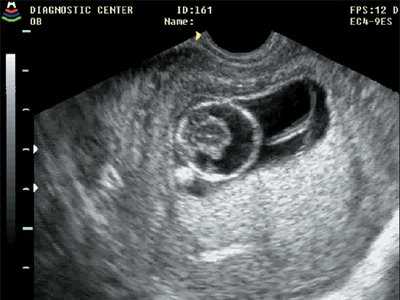

Рис. 3. Голопрозэнцефалия, беременность 11 недель 5 дней.